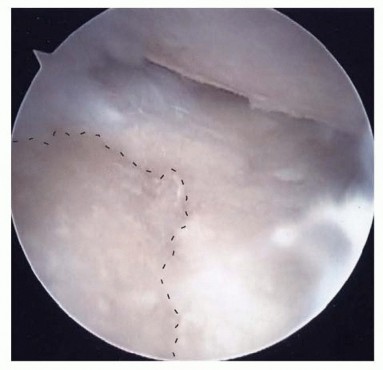

Image

The fundamental surgical peril of radial styloidectomy lies in the inadvertent detachment of the RSC and LRL ligaments. Biomechanical studies by Siegel and Gelberman, alongside volumetric analyses by Nakamura et al., have definitively established the "safe zones" for resection. A transverse resection of more than 3 to 4 millimeters from the tip of the styloid drastically compromises the origin of the RSC ligament. Loss of this ligamentous tether removes the primary restraint to ulnar carpal slide. Therefore, the osteotomy must be meticulously planned as a short, oblique cut—starting distally at the radial margin and exiting proximally within the scaphoid fossa—to decompress the impingement zone while rigorously preserving the volar capsular footprints.